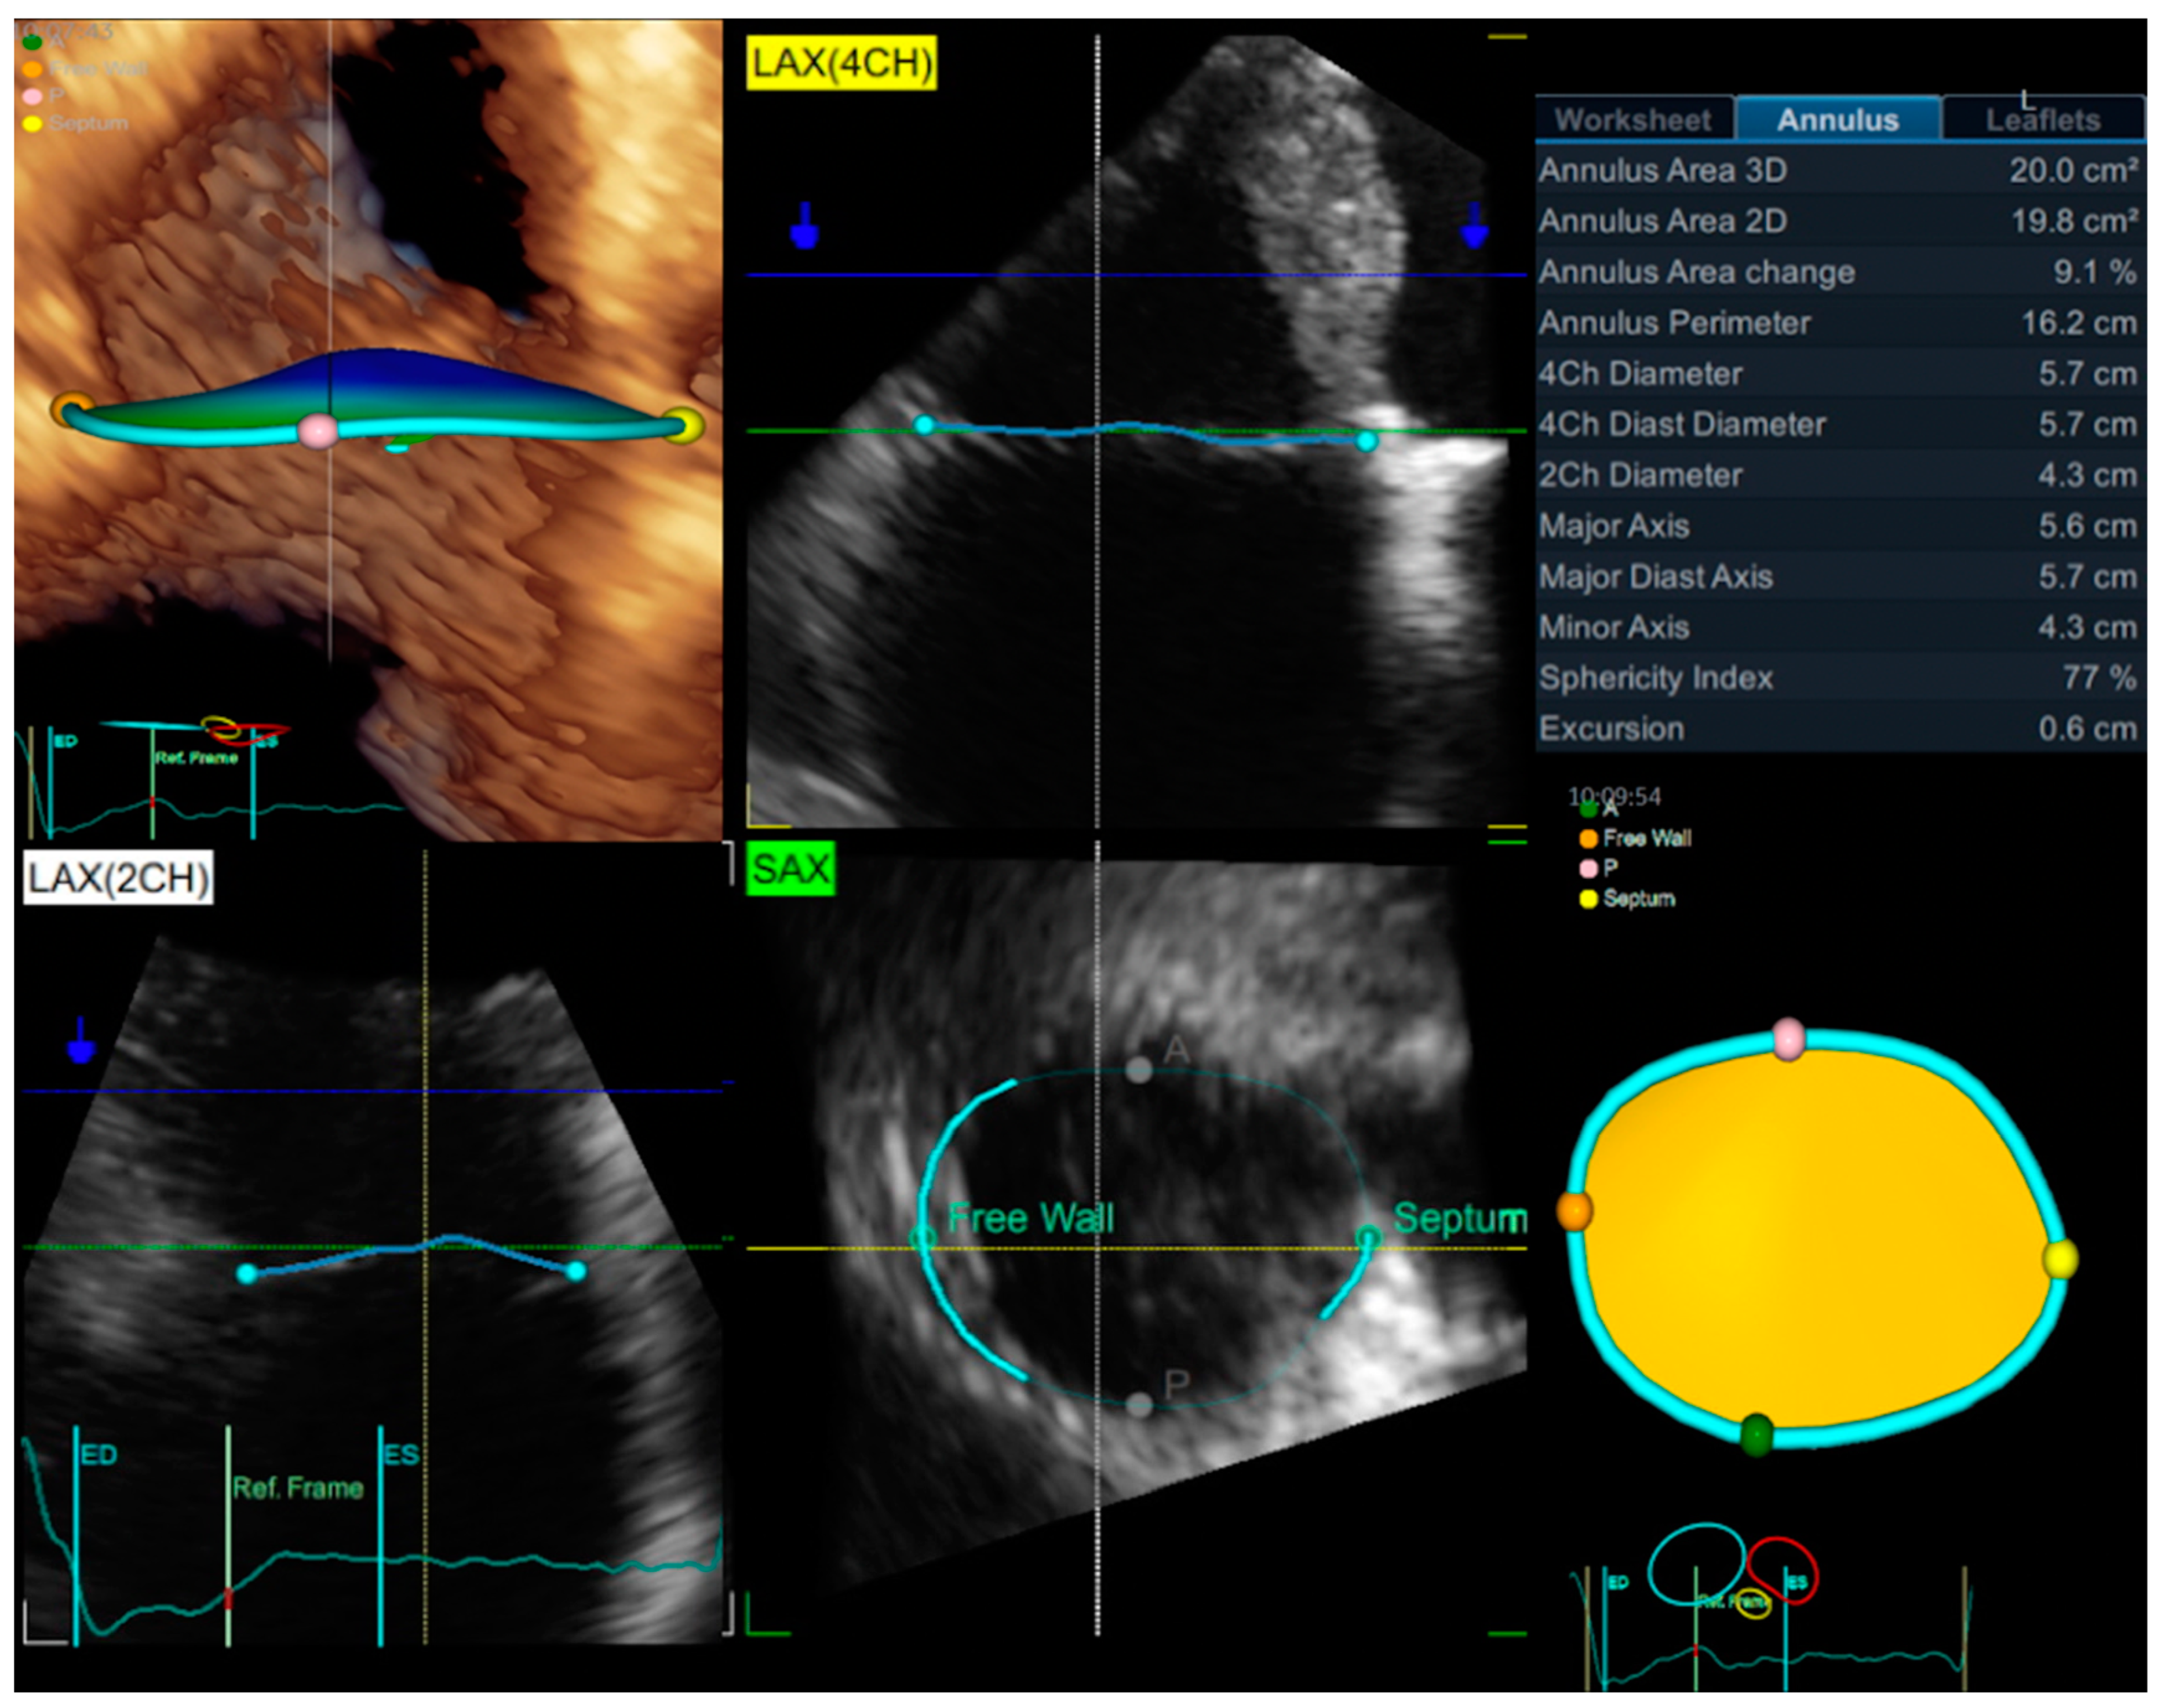

- Addetia, K.; Muraru, D.; Veronesi, F.; Jenei, C.; Cavalli, G.; Besser, S.A.; Mor-Avi, V.; Lang, R.M.; Badano, L.P. 3-Dimensional Echocardiographic Analysis of the Tricuspid Annulus Provides New Insights Into Tricuspid Valve Geometry and Dynamics. JACC Cardiovasc. Imaging 2019, 12, 401–412. [Google Scholar] [CrossRef]

- Volpato, V.; Lang, R.M.; Yamat, M.; Veronesi, F.; Weinert, L.; Tamborini, G.; Muratori, M.; Fusini, L.; Pepi, M.; Genovese, D.; et al. Echocardiographic Assessment of the Tricuspid Annulus: The Effects of the Third Dimension and Measurement Methodology. J. Am. Soc. Echocardiogr. Off. Publ. Am. Soc. Echocardiogr. 2019, 32, 238–247. [Google Scholar] [CrossRef]

- Miglioranza, M.H.; Mihăilă, S.; Muraru, D.; Cucchini, U.; Iliceto, S.; Badano, L.P. Dynamic changes in tricuspid annular diameter measurement in relation to the echocardiographic view and timing during the cardiac cycle. J. Am. Soc. Echocardiogr. Off. Publ. Am. Soc. Echocardiogr. 2015, 28, 226–235. [Google Scholar] [CrossRef]

- Miglioranza, M.H.; Mihăilă, S.; Muraru, D.; Cucchini, U.; Iliceto, S.; Badano, L.P. Variability of Tricuspid Annulus Diameter Measurement in Healthy Volunteers. JACC Cardiovasc. Imaging 2015, 8, 864–866. [Google Scholar] [CrossRef] [PubMed]

- Muraru, D.; Addetia, K.; Guta, A.C.; Ochoa-Jimenez, R.C.; Genovese, D.; Veronesi, F.; Basso, C.; Iliceto, S.; Badano, L.P.; Lang, R.M. Right atrial volume is a major determinant of tricuspid annulus area in functional tricuspid regurgitation: A three-dimensional echocardiographic study. Eur. Heart J. Cardiovasc. Imaging 2020, 22, 660–669. [Google Scholar] [CrossRef] [PubMed]